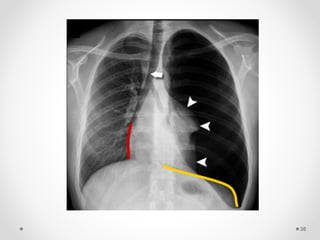

Deep costophrenic sulcus

Lucent cardiophrenic sulcus

Sharp mediastinal contour

Double diaphragm sign

subpulmonic pneumothorax